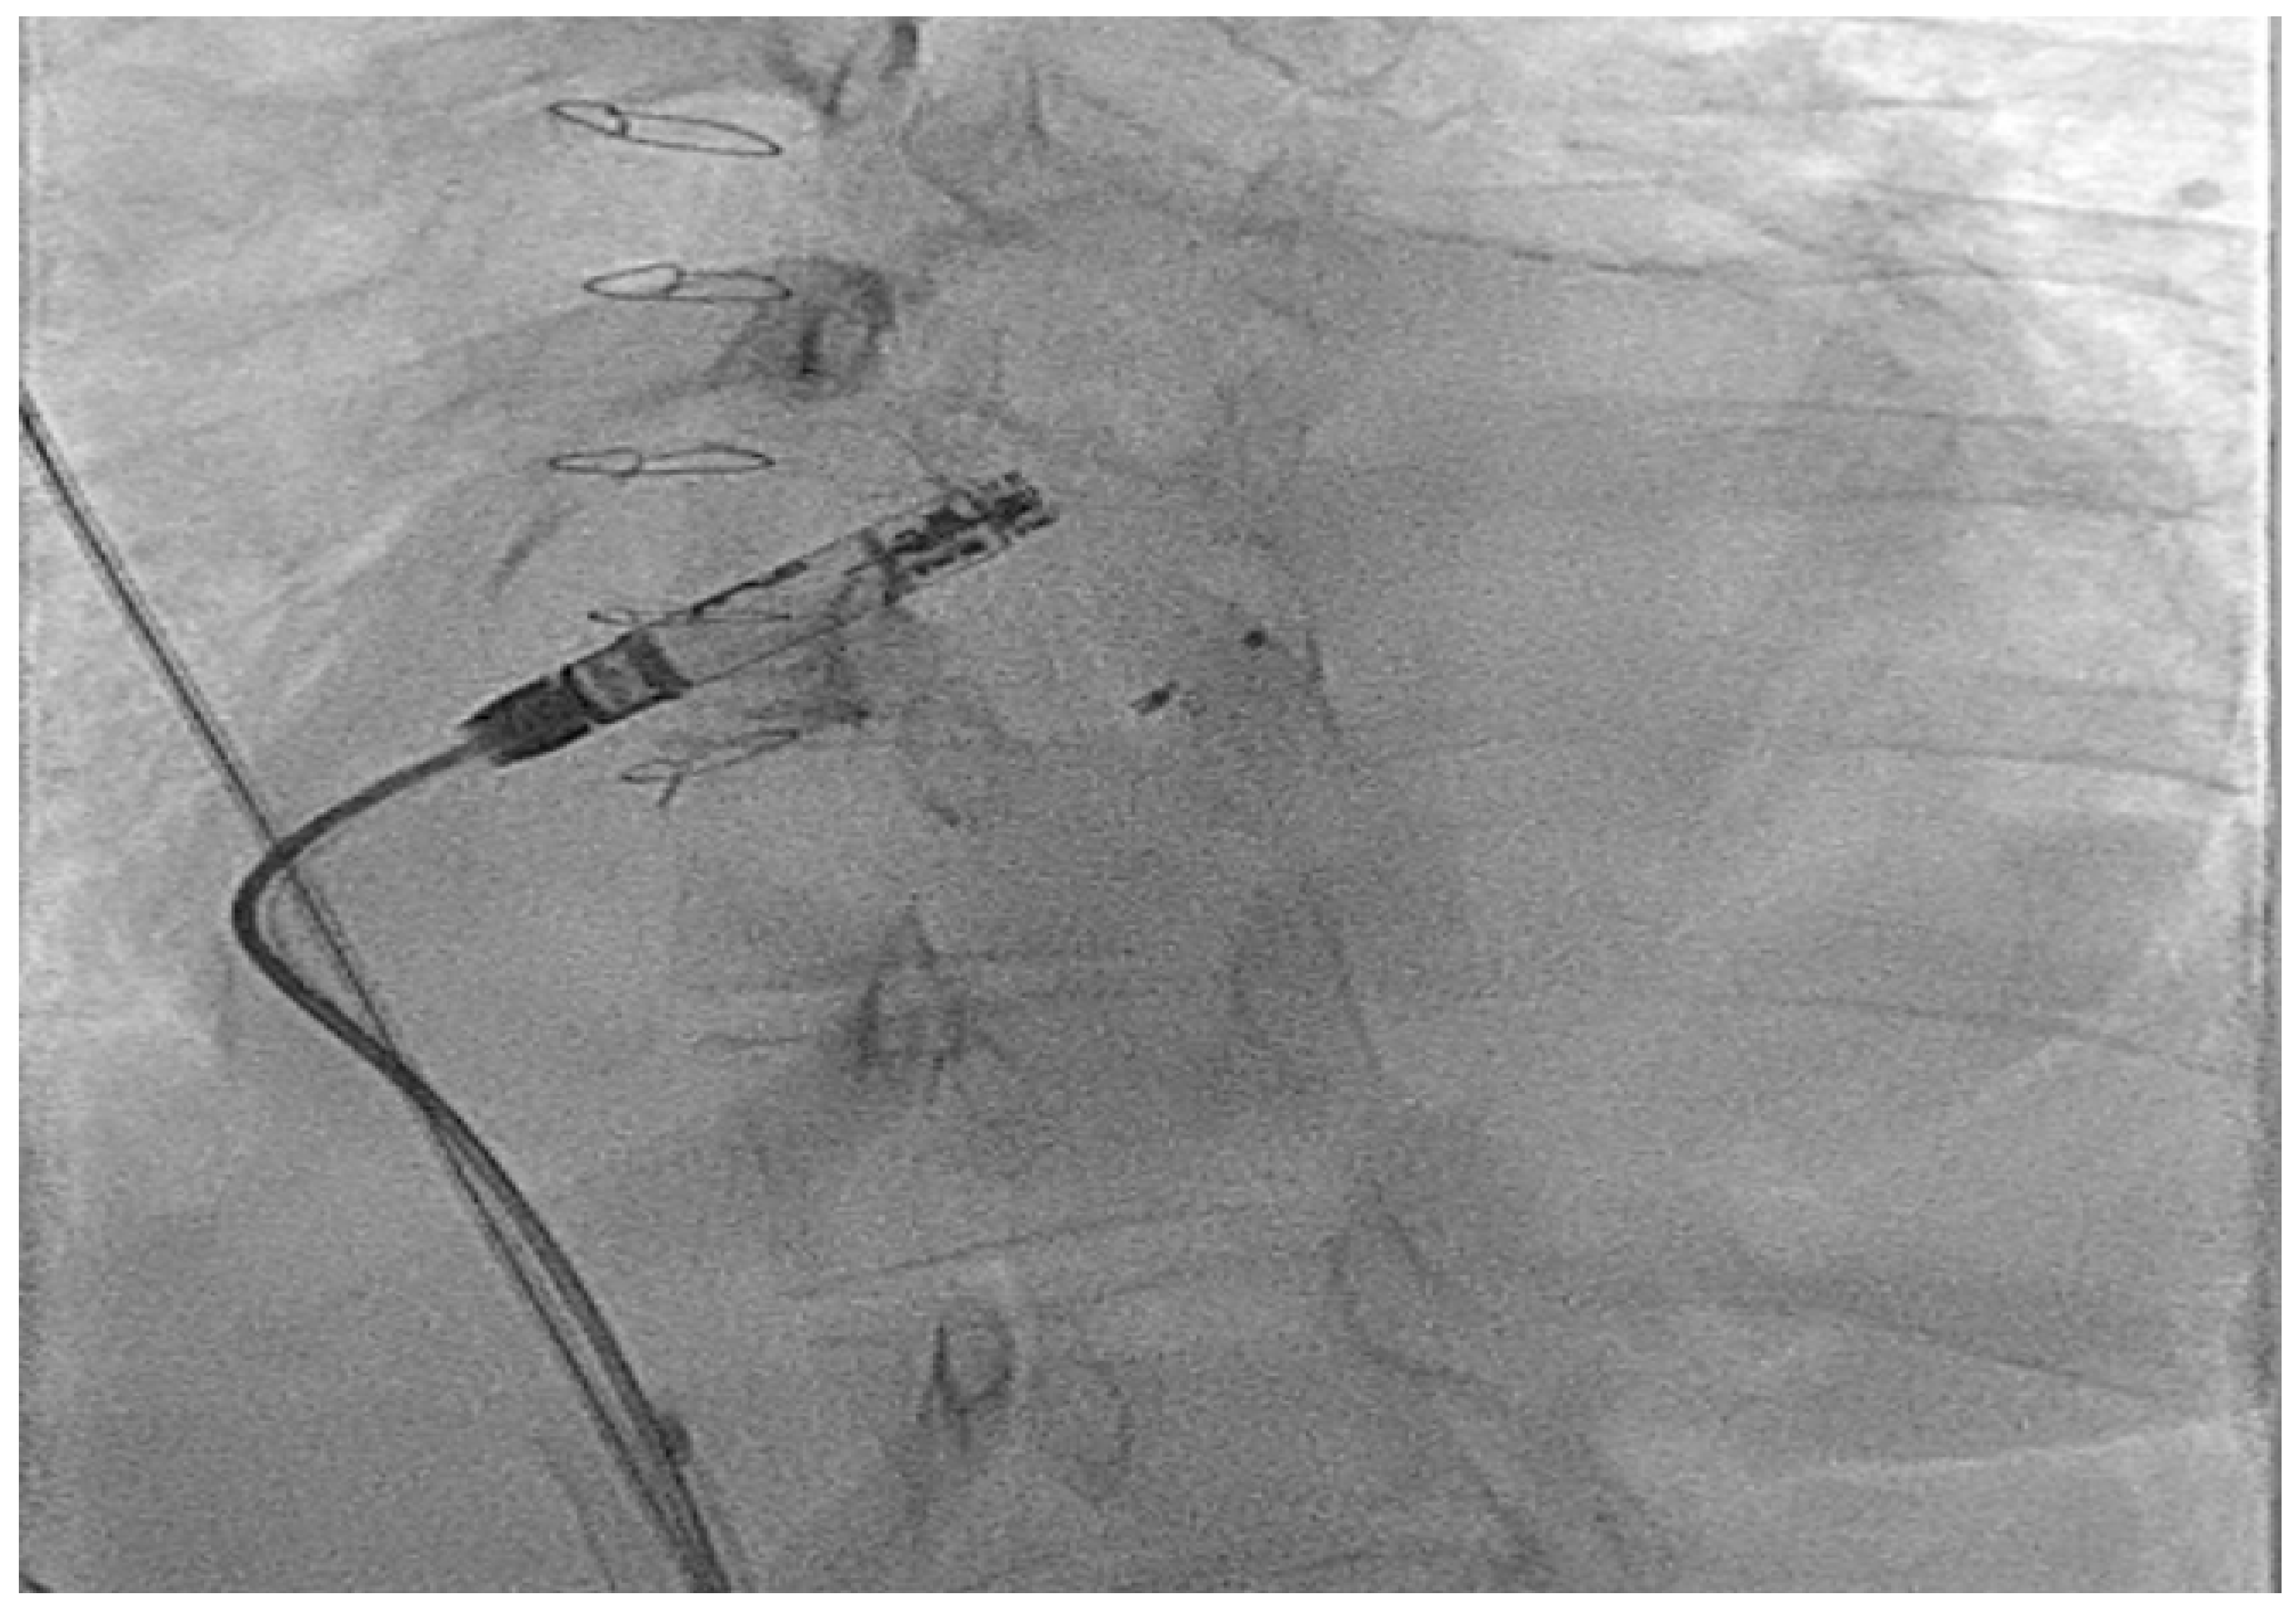

- Hayle, P.; Altayeb, F.; Hale, A.; Rao, A.; Ashrafi, R. Case report demonstrating novel approaches for leadless pacemaker implantation in the single ventricle heart. Eur. Heart J. Case Rep. 2025, 9, ytaf146. [Google Scholar] [CrossRef]

- Goulden, C.J.; Khanra, D.; Llewellyn, J.; Rao, A.; Evans, A.; Ashrafi, R. Novel approaches for leadless pacemaker implantation in the extra-cardiac Fontan cohort: Options to avoid leaded systems or epicardial pacing. J. Cardiovasc. Electrophysiol. 2023, 34, 2386–2392. [Google Scholar] [CrossRef]